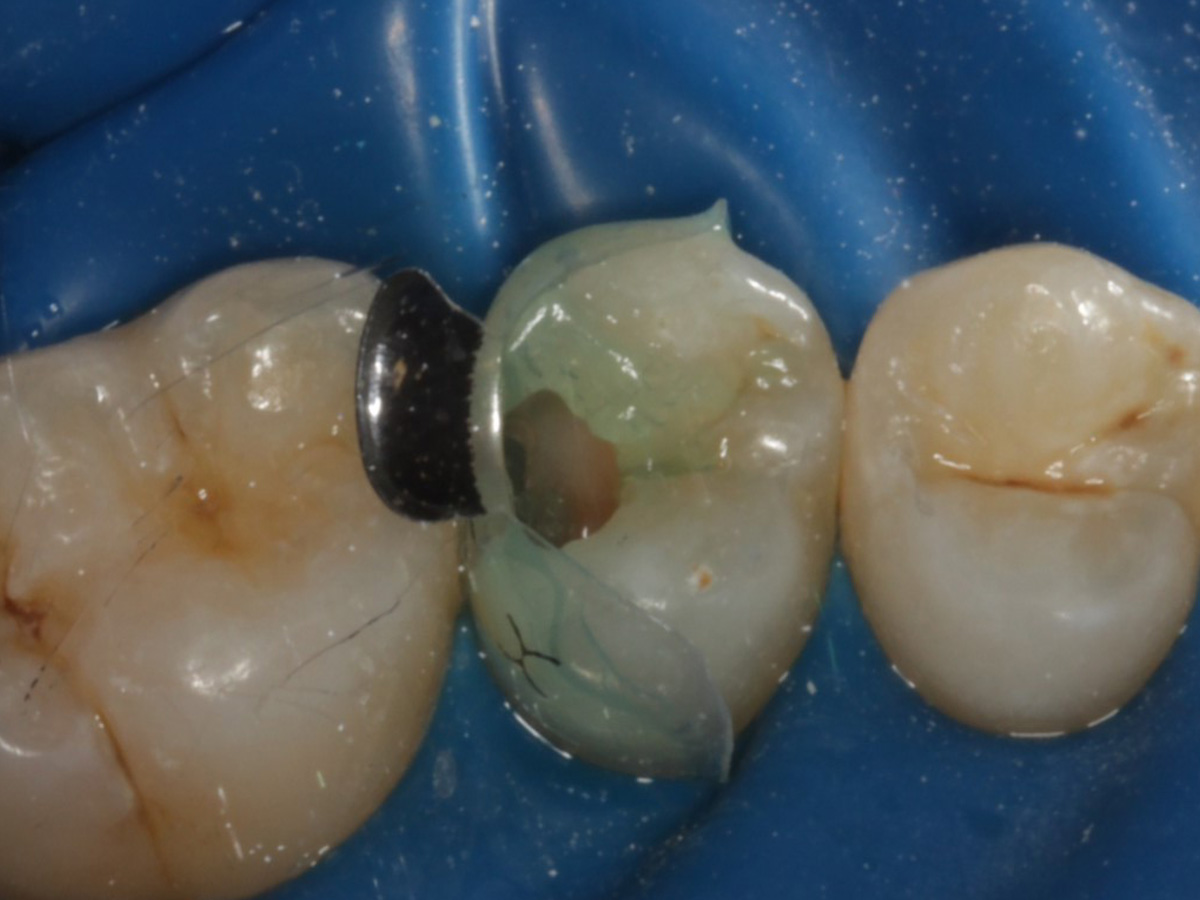

Abbildung 1

Approximalraumkaries an Zahn 25 distal

Abbildung 5

Defektdarstellung

Nach Applikation der Matrize: Evolve Schwarz Prämolar- 7 mm; Schmelzätzung